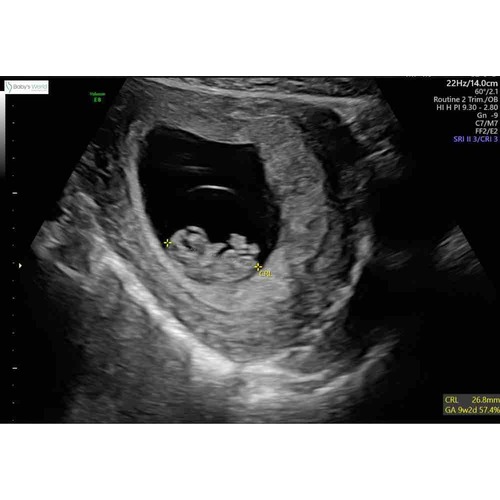

Mijn echo van afgelopen maandag bij 7+4. Helemaal onderin gelegen met het hoofdje rechts, twee ‘stompjes’ die uit moeten groeien tot armpjes. Daarboven het vruchtzakje. Zo bijzonder hoe ze dat allemaal al kunnen zien! Ik ben benieuwd naar de volgende echo.